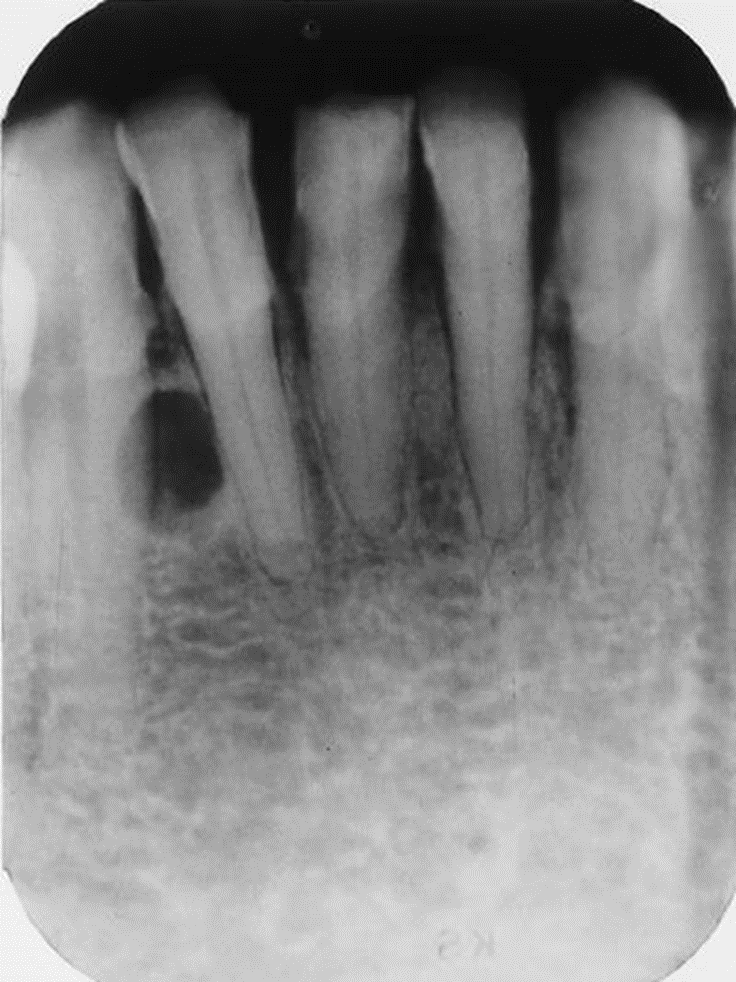

21. What is the most likely diagnosis for these periapical lesions of the mandibular incisors?